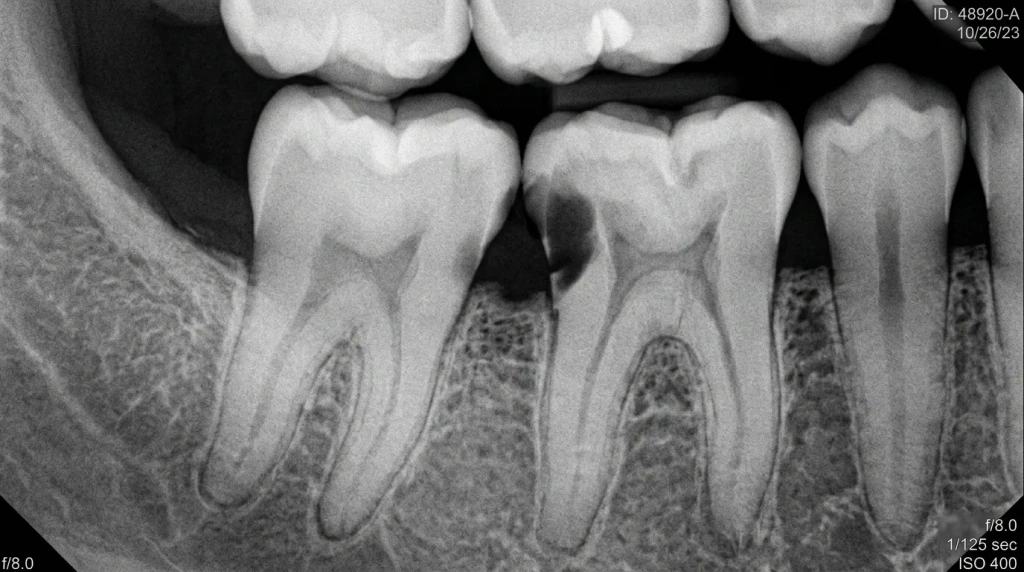

Рентгеновский снимок, показывающий кариозное поражение в межзубном пространстве на ранней стадии.

Выявление кариеса в межзубных пространствах требует профессионального подхода, поскольку самодиагностика часто бывает ошибочной. В России стандартный осмотр сочетается с цифровой рентгенографией, которая минимизирует облучение и дает четкие изображения. Бите-крылатые снимки — золотой стандарт для межзубных зон, позволяющий увидеть деструкцию на уровне дентина.